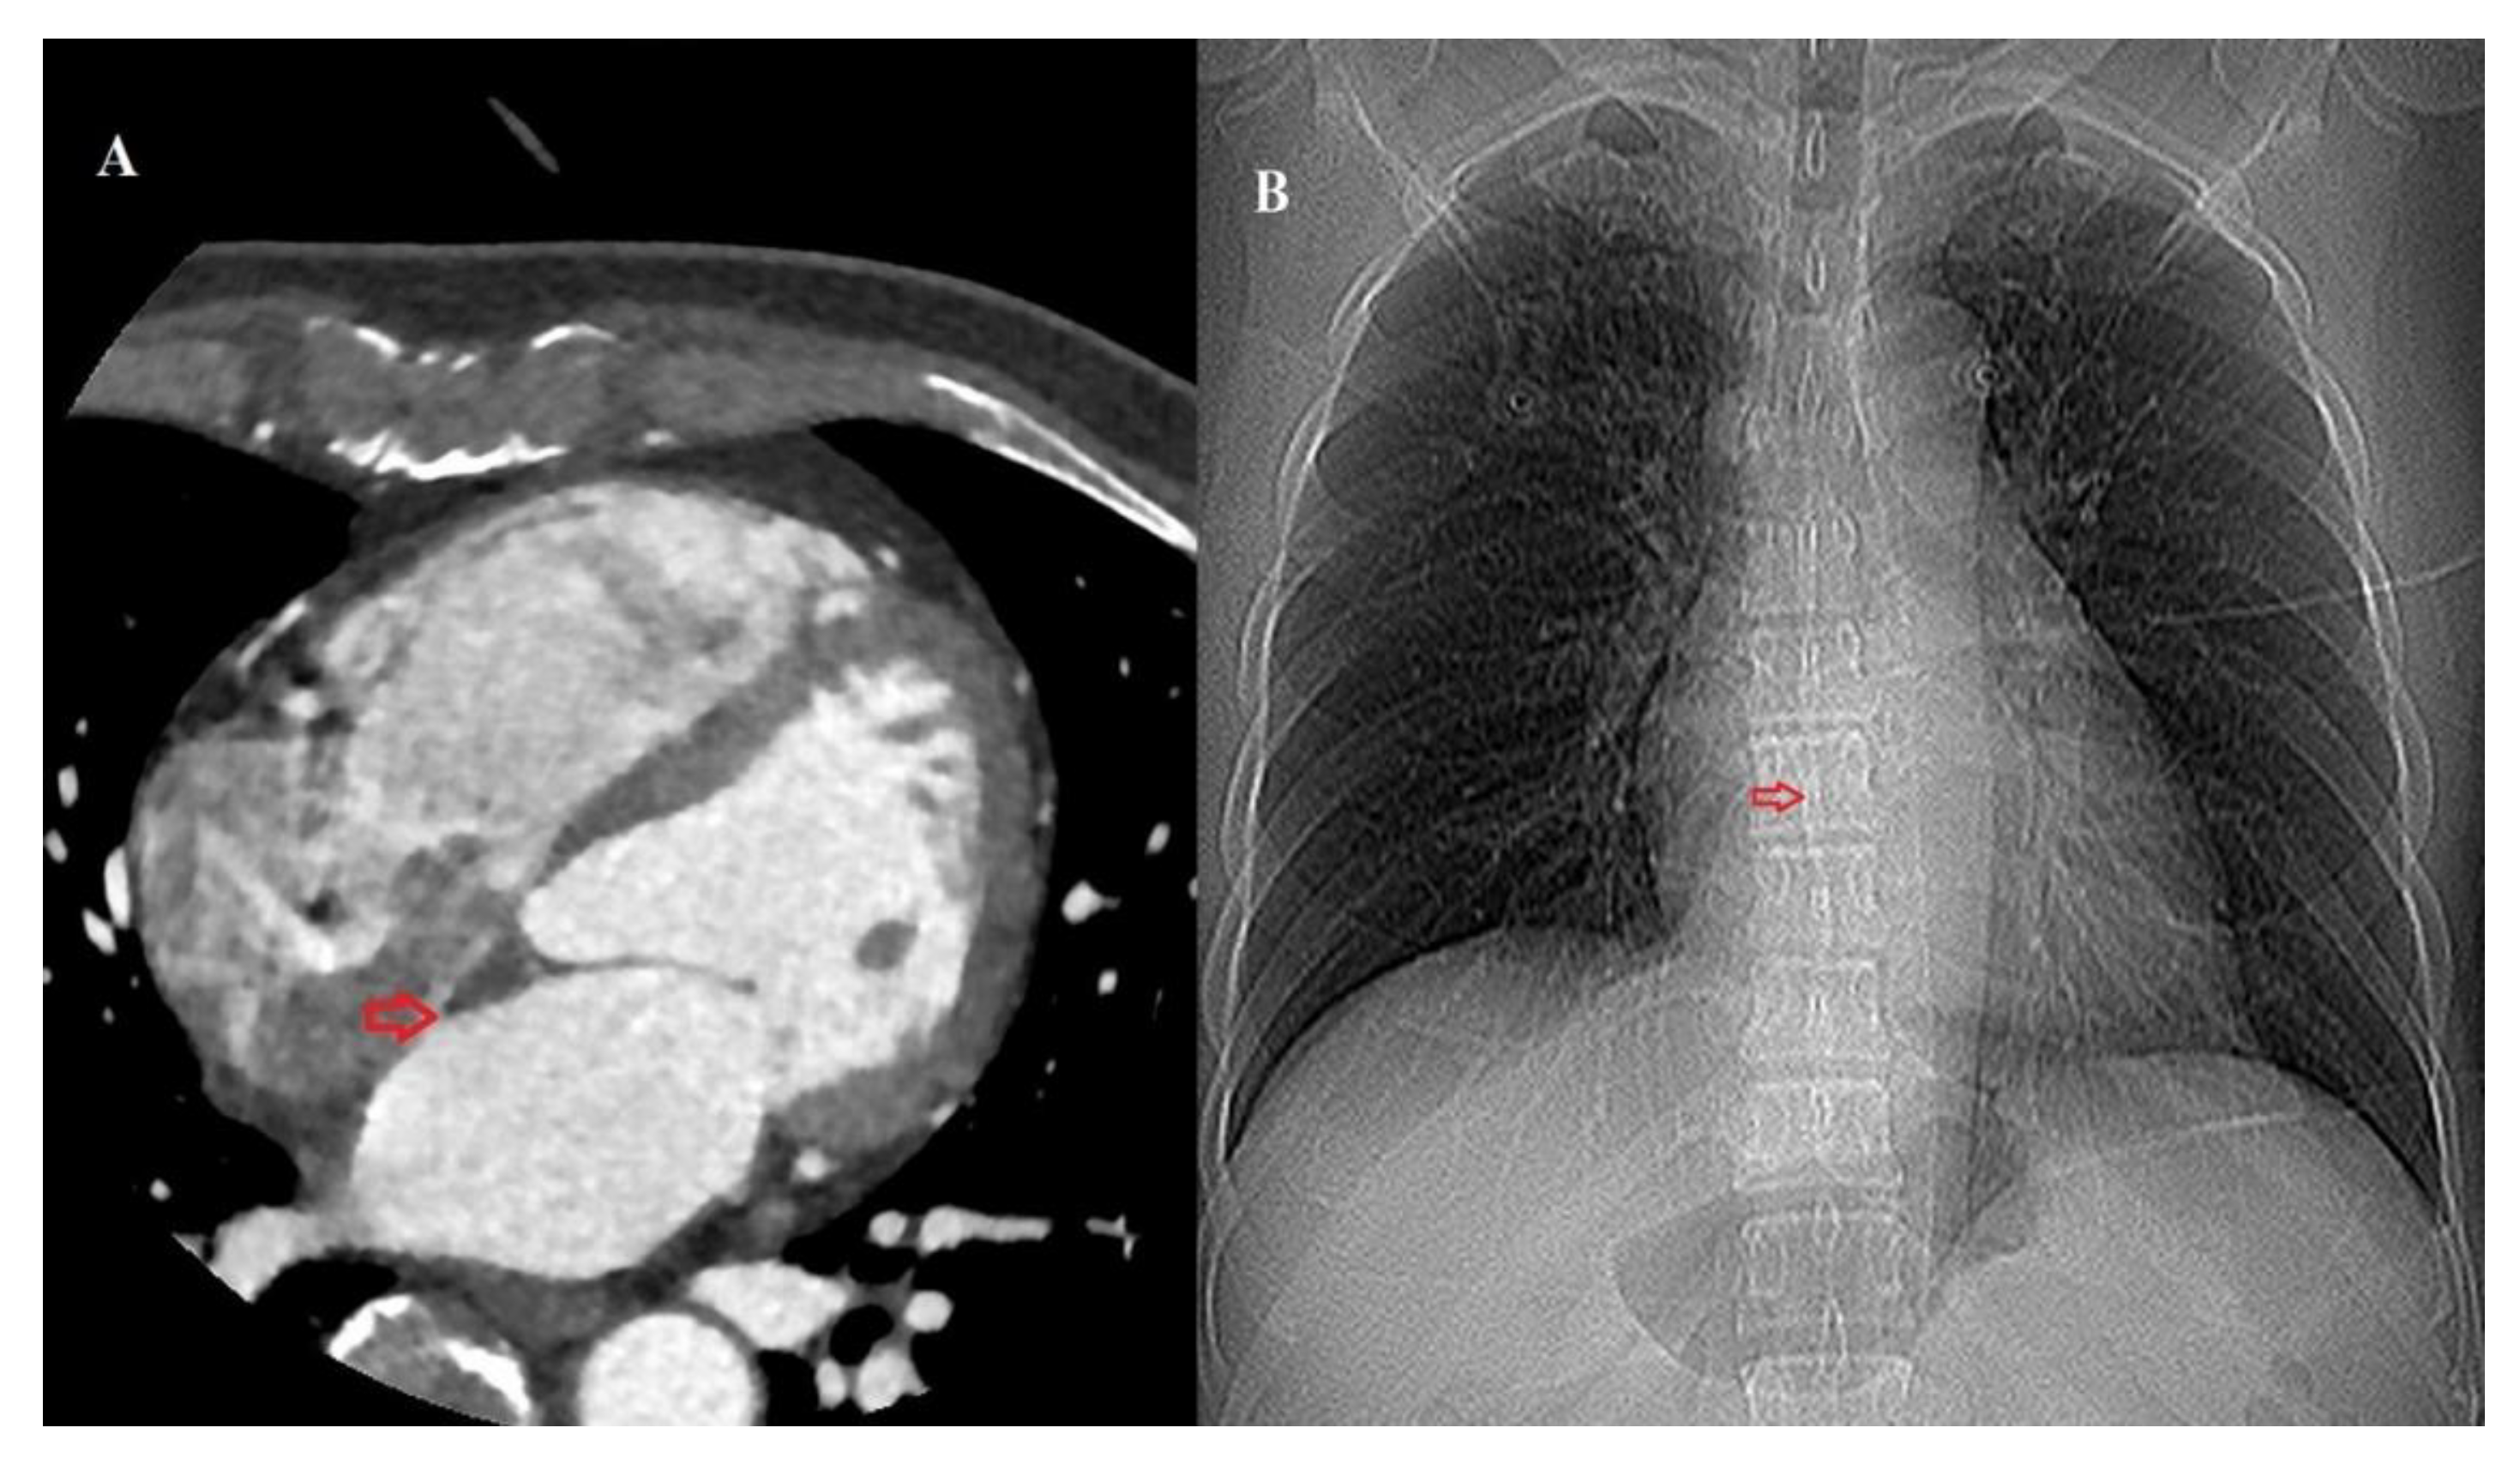

2.3. Image Acquisition and Measurement

| Carina–FO (cm) | 6.8 ± 0.8 | 7.3 ± 1.2 | 7.5 ± 0.7 | <0.001 |